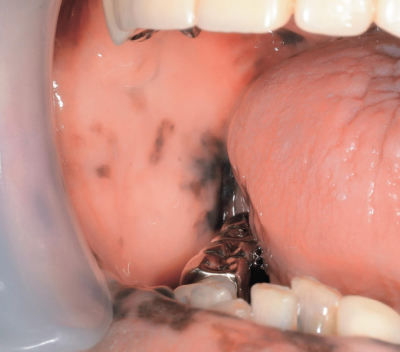

65歳の男性。右側頰粘膜と下唇の異常を主訴として来院した。3か月前に気付いたが、疼痛がないためそのままにしていたという。初診時の口腔内写真と生検時の H-E 染色病理組織像を別に示す。

引き続き精査すべき疾患はどれか。2つ選べ。

e. 消化管ポリポーシス